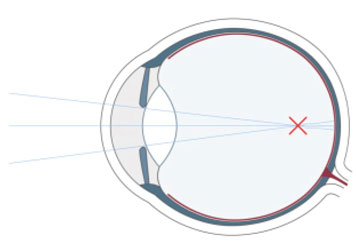

Wer unscharf sieht, war bisher gezwungen, sich mit Brillen und Kontaktlinsen zu behelfen. Die Refraktive Chirurgie ist mit dem LASIK-Verfahren in der Lage, die Sehschwäche am Auge selbst zu korrigieren. Das LASIK-Verfahren hat sich als die erfolgreichste und weltweit am häufigsten angewandte Methode zum Augenlasern etabliert.

Bei Kurzsichtigkeit, Weitsichtigkeit und Alterssichtigkeit sowie bei einer Hornhautverkrümmung setzen wir einen Augenlaser ein, der sich auf dem allerneuesten Stand der Technik befindet. Das Augenlasern führen wir ambulant durch, der Eingriff selbst dauert nur wenige Minuten. Welche Methode beim Augenlasern zum Einsatz kommt, wie sich der Ablauf beim genau gestaltet und welche Kosten hierdurch entstehen, ist abhängig von der vorliegenden Fehlsichtigkeit.